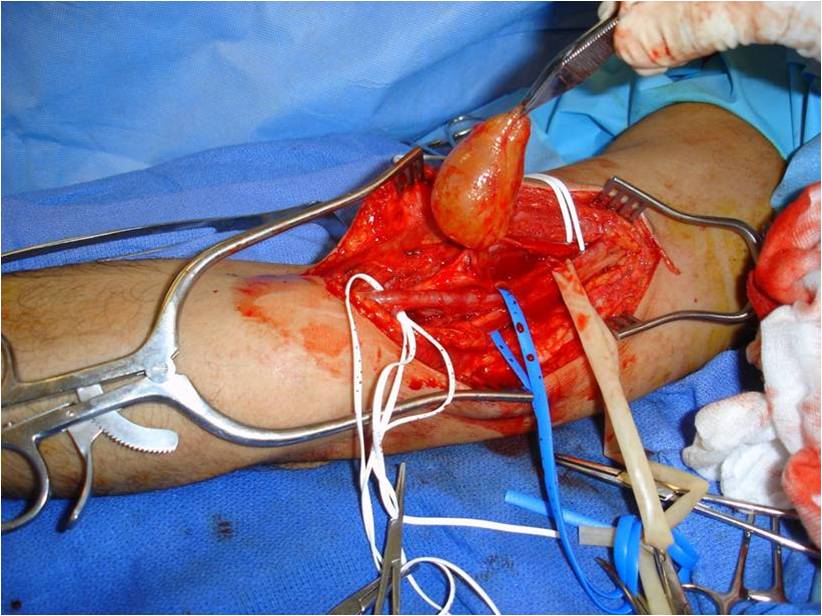

Treatment

• Surgical Excision (Fig. 9, 10, 11)

o Marginal Excision; Spare nerve from excision

The epineurium is opened carefully on a side opposite nerve fascicles and the mass is gently separated from the nerve fascicles and epineurium.

o Rarely if ever recurs

Fig. 9-11 Intraoperative photographs demonstrate medial approach to the arm and neurovascular dissection, including; median nerve and brachial artery. Schwannoma is easily distinguished in the median nerve. The sheath of the nerve is opened on the opposite side of the splayed out nerve fascicles and the tumor removed. The nerve was spared.